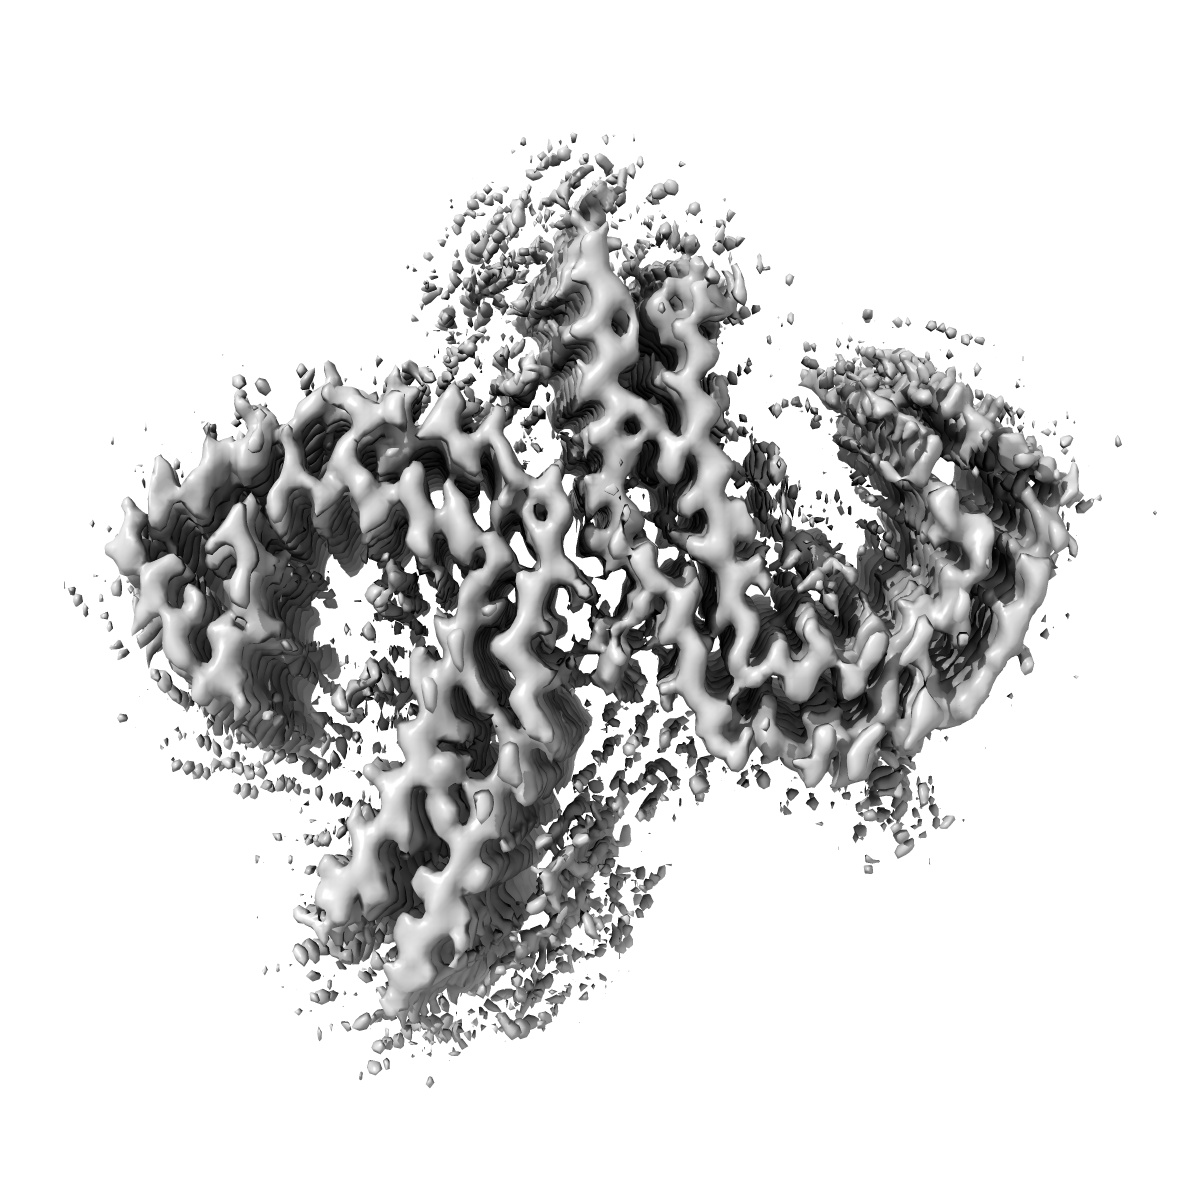

Straight Filaments purified from Down Syndrome individual brain tissue applied to graphene oxide antibody affinity grids

Cryo-EM structures reveal tau filaments from Down syndrome adopt Alzheimer's disease fold.

Ghosh U, Tse E, Yang H , Shi M, Caro CD, Wang F, Merz GE, Prusiner SB, Southworth DR, Condello C

(2024) Acta Neuropathol , 12 , 94 - 94